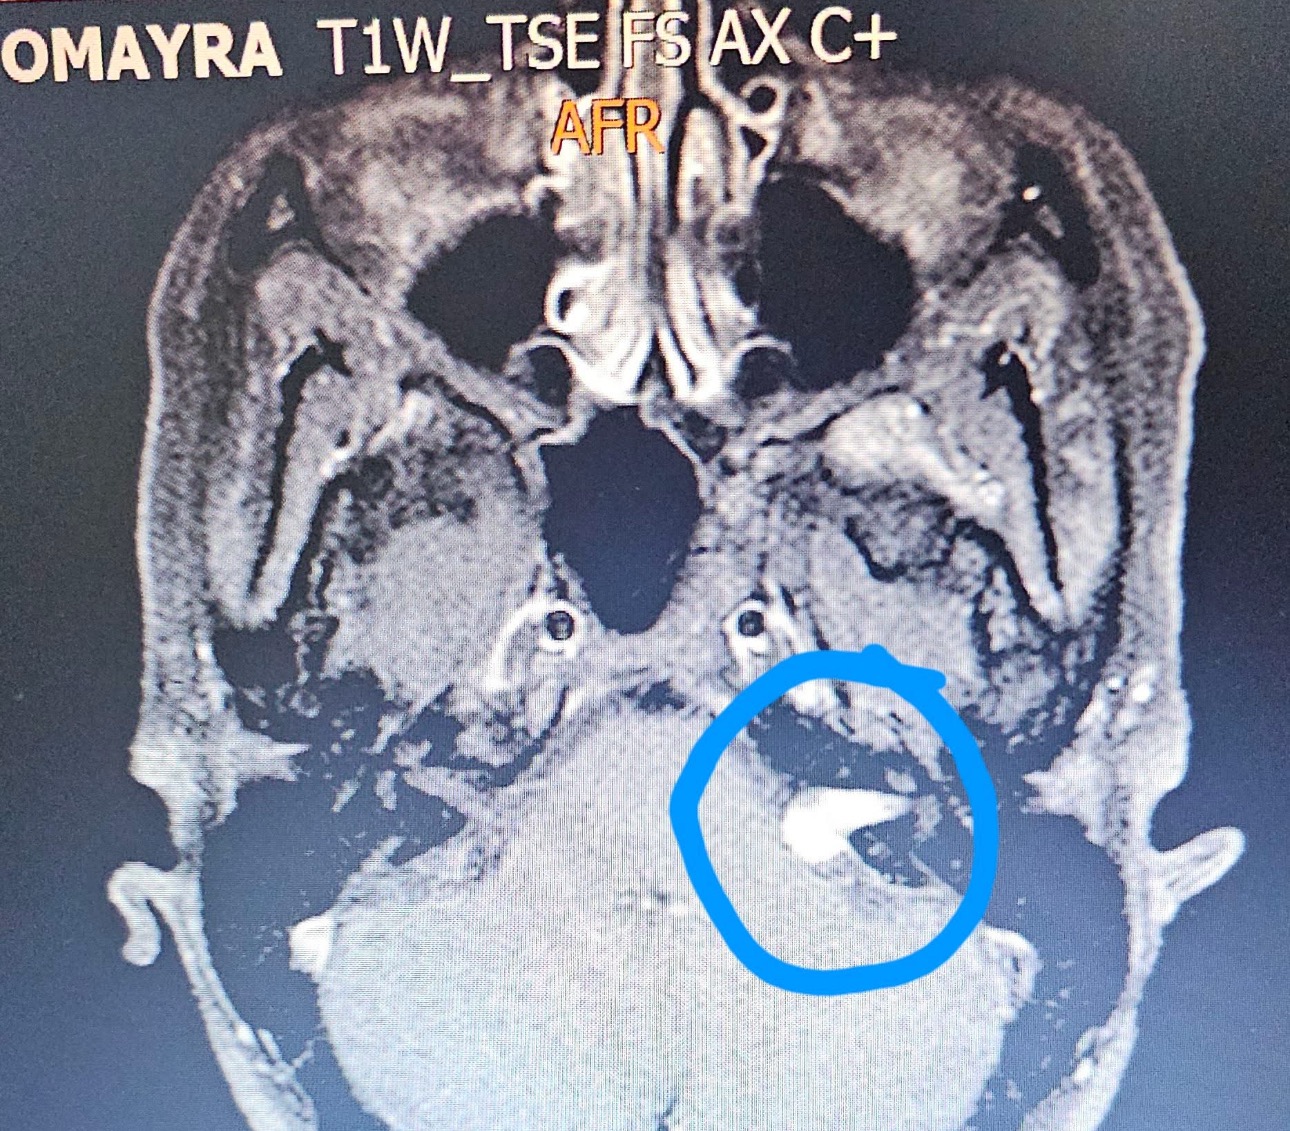

Hola, mi nombre es Francés Omayra para los que no conocen mi situación llevo batallando con esto desde el año 2023 aproximadamente, llevo conmigo un Schwannoma Vestibular ( Es un tumor benigno que se origina en las células que rodean el nervio vestibular, los ramos del nervio afectan el equilibrio y la audición) y puede afectar más áreas si continúa creciendo…

En mi caso me esta afectando la audición...